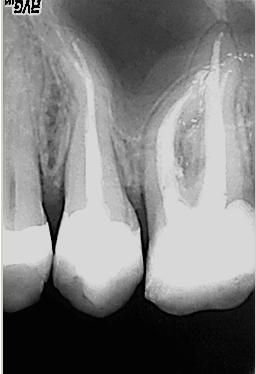

WF-Langzeitkontrolle

WF-Langzeitkontrolle nach 5 Monaten im November 2003. Als abschließende, für den Langzeiterfolg zwingend notwendige Maßnahme ist nun die Überkronung des Zahnes geplant